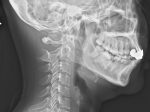

寝違えは「急性疼痛性頸部拘縮」とも言われ頸部周辺の人体や筋肉に急な炎症が起こっている状態です。

寝違えると、起きるためにある姿勢をとった時に頸椎の痛みを覚えます。

頚椎症は背中と頭をつなぐ頸椎の骨と骨の間のクッションの役目をする椎間板の厚みがなくなって、骨と骨とが当たってしまうことで痛みが起こる病気です。

椎間板が薄くなるのは加齢や生活習慣が関係し、頸椎を酷使したり、悪い姿勢が長く続くと関節に負担がかかり、椎間板の厚みが減ってきます。

頚椎症の症状は首や肩甲骨の周辺に痛みが出たり肩こりの症状が出ても手のしびれがない初期段階、片側の方や首、腕から手にかけて痛みやしびれが起きたり力が入りにくくなるという症状が出る第2段階、両手足のしびれや動きが悪くなりひどい場合は、排泄が困難になったり、階段を下りたり、ボタンをかけることができにくくなるなどの症状も出る第3段階があります。

手や足までもがしびれたりするのは椎間板の変形とともに骨までが変形して骨棘ができてそれが神経根にあたるためです。

頚椎症はひどくなると首や肩だけでなく神経を通じて手足や全身にも症状が及ぼされます。